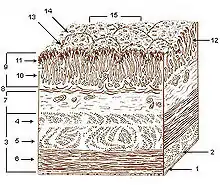

Mucosa

The mucosal layer consists of a epithelial layer, and its underlying supportive tissue, the Lamina Propria. It is separated from the submucosal layer by the Muscularis Mucosa. The epithelial layer varies from section to section of the gut. In the oesophagus it is a non-cornified stratified squamous epithelium; in the stomach it is mainly mucosal cells; the small intestine and large intestine are characterized by absorptive cells, with many mucous producing goblet cells. In the absorptive sections of the intestine, the surface are for absorption is greatly increased by finger-like projections into the lumen called villi, and the absorptive cells themselves also have small projections of microvilli, giving them the appearence of a brush border when viewed with a light microscope.

The lamina propria contains lymph and blood vessels which drain into larger vessels in the submucosal layer. Also in the lamina propria, particularly in the absorptive layers are numerous immune cells, wandering macrophages and lymphocytes, as well as aggregations of lymphoid tissue called called Peyers patches. By some estimates 80% of the body's lymphoid tissue is in the intestine.

The cell-to-cell junctions are of the epithelia are mainly tight junctions. In the stomach there are very little or no gaps between the epithelial cells, but in the absorptive sections there is a certain amount of 'leakiness' so that water and some solutes can go between the cells rather than through them. The degree of leakiness is variable and is to some extent under hormonal control.

Submucosa

The submucosa consists of connective tissue with larger blood and lymph vessels. It is separated from the mucosa by the muscularis mucosa. Also in the submucosal layer is the submucosal plexus, part of the enteric nervous system. The muscularis mucosa probably acts to propel the contents of the mucosal glandular lumens and crypts (see below) into the lumen and also to enhance contact of the cells with the contents of the lumen.